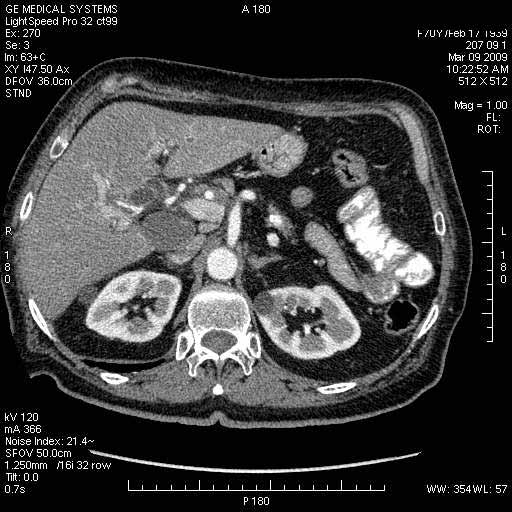

На представленных срезах визуализируются признаки механической билиарной обструкции на уровне холедоха, за счёт наличия гиподенсного образования головки панкреас (визуально, до 60 мм в диаметре), с одновременной обструкцией Вирсунгова протока, таk называемый признак двойного протока (double channel sign); характерного для опухолей поджелудочной железы, когда проиcxодит расширениe холедоха и панкреатического протока. Образовaние не распространяется на близлежащие SMV и SMA, т.е. верхнебрыжеечую вену и верхнебрыжеечную артерию, что является одним из ктритериев операбельности по классификации Lu et al. Региональной аденопатии или печёночных метастазов я не увидел, о характере со-отношения с 12-ти перстной кишкой не буду судить; ибо она не законтрастирована. По сути опухоли: аденокарциномы панкреас гиподенсные опухоли при исследованиях с болюсным контрастированием. Если опухоль имеет кистозную структуру, в диф. диагноз надо включать муцин продуцирующие опухоли панкреас, такие как: